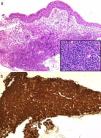

Clinical ObservationA 75-year-old male with a history of hypertension for which he was on medical treatment, allergic to iodinated contrast, presented in January 2004 with fever and abdominal pain. Physical examination revealed tenderness in the left hypochondrium. Computed tomography (CT) of the abdomen showed splenomegaly with multiple hypodense nodular lesions and infradiaphragmatic adenopathies in the mesenteric-celiac region and perivascular space of the abdominal aorta. A splenectomy was performed; spleen histology was indicative of DLBCL. The patient was treated with the immunochemotherapy regimen R-CHOP (rituximab, cyclophosphamide, adriamycin, vincristine and prednisone), achieving complete response. In June 2010, he presented with left pleuritic pain and moderate-effort dyspnoea. Physical examination revealed hypophonesis in the left pulmonary field. A chest CT scan was performed, showing stenosis of the left main bronchus and ipsilateral hilar adenopathies leading to left upper lobe collapse (Fig. 1a). Due to a suspected lung neoplasm, bronchoscopy was performed, which showed the presence of an endobronchial mass with a smooth surface obstructing the entry to the left upper lobe. Bronchial biopsy was carried out, but the material obtained was insufficient to establish a definitive diagnosis. A second biopsy obtained material that was suspicious for malignant cells but the sample size did not enable immunohistochemical techniques to be applied; it was therefore decided to perform a bronchial biopsy using a cryoprobe (Fig. 1b), obtaining a larger fresh sample of the lesion. Histological examination showed diffuse infiltration of the corium by a lymphoid proliferation of large atypical cells with numerous mitoses, with no infiltration of the bronchial epithelium (Fig. 2a). Immunohistochemical techniques showed a CD20-positive neoplastic cell population (Fig. 2b), with co-expression of bcl-6 and CD10, and a proliferative index (ki-67) of 70%. In accordance with these findings, the patient was diagnosed with recurrent DLBCL. Second line treatment was initiated with R-ESHAP (rituximab, etoposide, methylprednisolone, cisplatin and cytarabine), achieving a second complete remission. The patient is currently awaiting an autologous haematopoietic stem cell transplant.

In the case presented, bronchial biopsies of the lesion were performed on two occasions using conventional forceps, but the samples obtained in both cases were insufficient to establish a specific histological diagnosis. Furthermore, this case involves several aspects that make it particularly interesting: from a diagnostic point of view, the low frequency of this disease and the rare presentation are noteworthy, as it is a recurrence of an endobronchial DLBCL in a patient previously diagnosed with extranodal DLBCL (splenic) and treated by chemotherapy and splenectomy with complete remission for years and, the diagnostic technique used to perform the histological study which enabled (as well as the application of immunohistochemical techniques) the integrity of the bronchial epithelium to be visualised (Fig. 2), ruling out other more common diagnoses such as mucosa-associated lymphoid tissue (MALT) lymphoma.